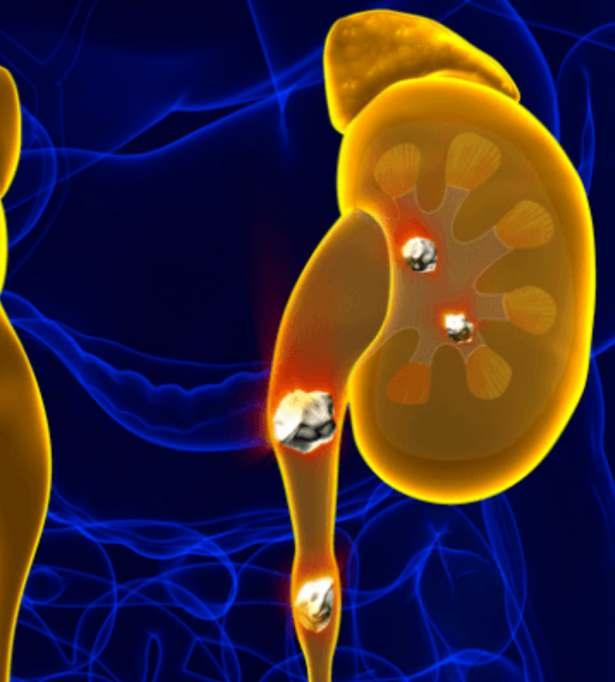

Piedras en el riñón y vejiga

Cálculos renales

• Cirugía láser de próstata y piedra

• Laparoscopía urológica

• Riñones • Cáncer urogenital

• Cirugía percutanea de cálculos

• Endourología • Varicocele

Próstata, Riñones, Vejiga, Genitales, Infecciones urinarias, Litiasis urinaria, Disfunción eréctil, Infertilidad.

Urología

- Piedras en los riñones